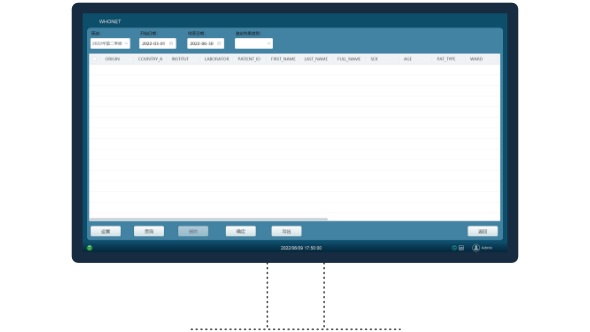

Smart

- • ID encyclopedia: Provides morphology and culture, pathogenicity and epidemiological information of common strains to help laboratories verify the accuracy of ID results when 2 or 3 ID results accounts;

- • Expert system: Indicates rare antimicrobial resistance, conflict antimicrobial susceptibility results and other information (Phenotype and treatment related) based on CLSI/EUCAST/FDA rules and several clinical guidelines;